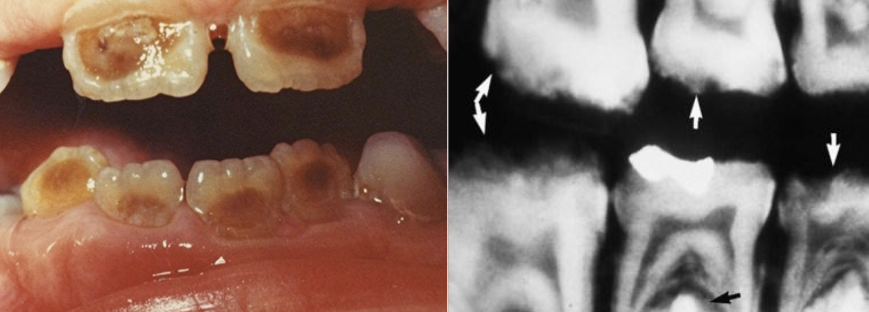

AD, AR, X-linked; both deciduous and permanent dentition are diffusely involved, affects enamel (soft, thin, easily damaged, susceptible to decay), dentin is exposed

amelogenesis imperfecta (AI)

Types of AI

hypoplastic (pitted), hypomaturation/ hypocalcification (snowcapped) AI with taurodontism

Clinical appearance of AI

yellow-brown to white pitted lesions, open bite, loss of contact

a hereditary condition of dentin in the absence of any systemic disease (opalescent dentin), AD, genetic mutation is DIFFERENT from osteogenesis imperfecta

dentinogenesis imperfects (DGI)

affects both dentition, steel-grey/ translucent/ opalescent crowns, brittle enamel

DGI

DGI radiographic presentation

bulbous crown, cervical constriction, pulp obliteration varies, expanded pulp = shell teeth